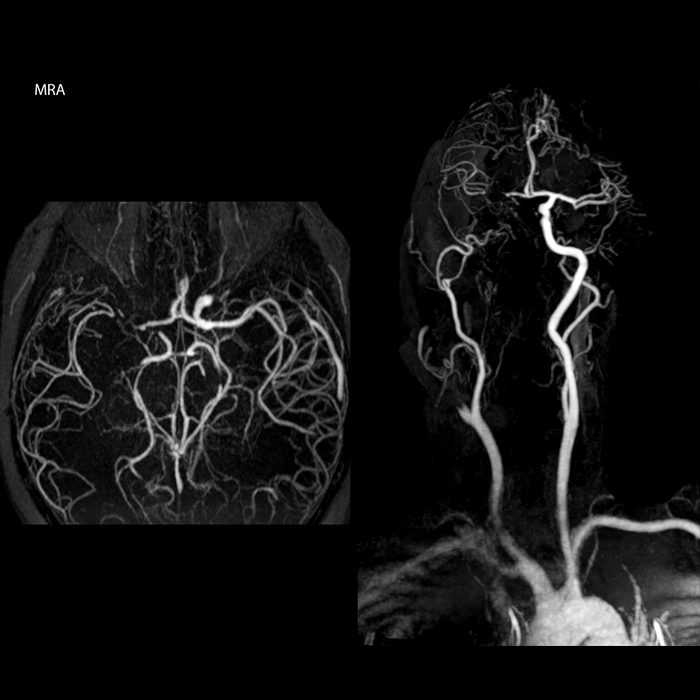

“In France, stroke is usually imaged with MRI, not CT, even for emergency treatment. This is because MRI helps us directly visualize ischemia in the acute phase, but can also help rule out differentials such as MS and hematoma. In addition, we can assess the intracranial and extracranial vessels during the same examination,” says Dr. Savatovsky.

“Ingenia provides great flexibility in the parameters setting. We can tune a sequence the way we want,” says Dr. Savatovsky. “For example, in a stroke exam we use a FLAIR sequence of about two minutes instead of the four-minute FLAIR we use for MS. The diffusion is 30 seconds, the T2*-weighted scan is 30 seconds, the angiography scan time is less than one minute. Ingenia is a great scanner in that situation; even with these fast sequences we can achieve good images with good SNR. When the first sequence tells us that it’s not an ischemic stroke but a hemorrhagic stroke, we may switch to a time-resolved angiography to look for vascular malformations and venous thrombosis.

“Every center is different, but for me the ideal protocol for stroke includes diffusion weighted imaging, FLAIR, and fast susceptibility imaging,” says Dr. Savatovsky. “Our fast susceptibility weighted imaging takes 50 seconds, so it’s as fast as T2*-weighted imaging. It visualizes hemorrhage but also the clots. We also do 3D MR angiography that provides information on cervical and brain vessels. If the patient does not need immediate treatment, or if additional information is needed to decide on treatment, we might also add perfusion imaging and post-contrast T1-weighted imaging.”